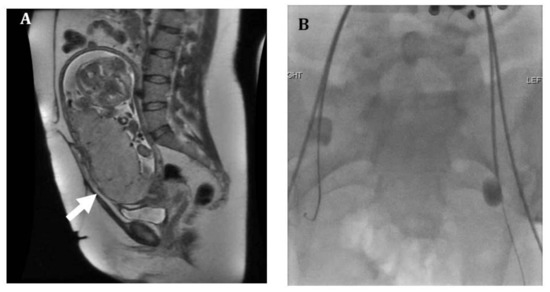

2. Imaging